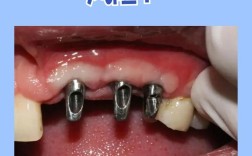

种植牙的核心原理是通过外科手术将纯钛种植体植入牙槽骨,待其与骨组织结合(骨结合)后,再在上方安装牙冠,这个过程就像“树扎根土壤”,牙槽骨的“质量”直接决定种植牙的稳定性、使用寿命和成功率。

临床中,医生判断能否种牙,不是只看“牙槽骨大小”,而是综合评估骨量是否满足种植体初期稳定性的需求(种植体植入后无松动,能承受咬合力),只要通过检查发现骨量与种植体直径、高度匹配,或可通过技术手段增加骨量,就能安全种牙。